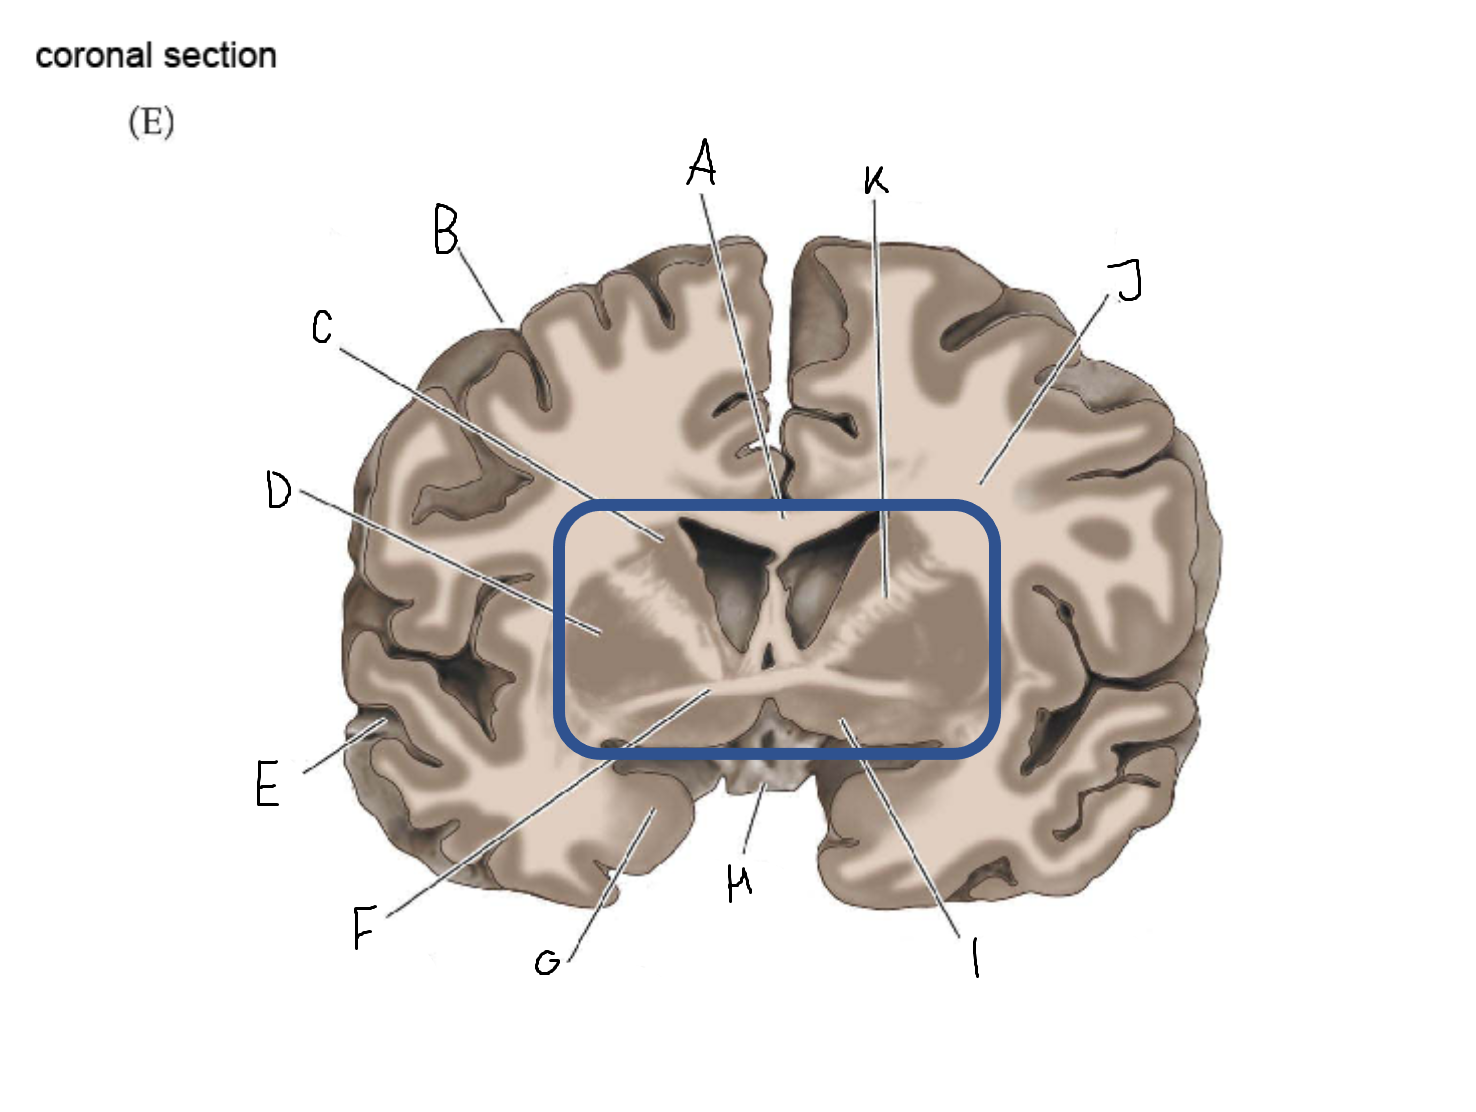

A

internal capsule (anterior limb)

B

caudate nucleus body

C

caudate nucleus head

D

putamen

E

caudate nucleus tail

F

thalamus

G

internal capsule (posterior limb)

B

anterior horn of lateral ventricle

C

head of caudate nucleus

D

internal capsule (anterior limb)

E

putamen

F

globus pallidus

G

Thalamus

H

External capsule

I

internal capsule (posterior limb)

J

tail of caudate nucleus